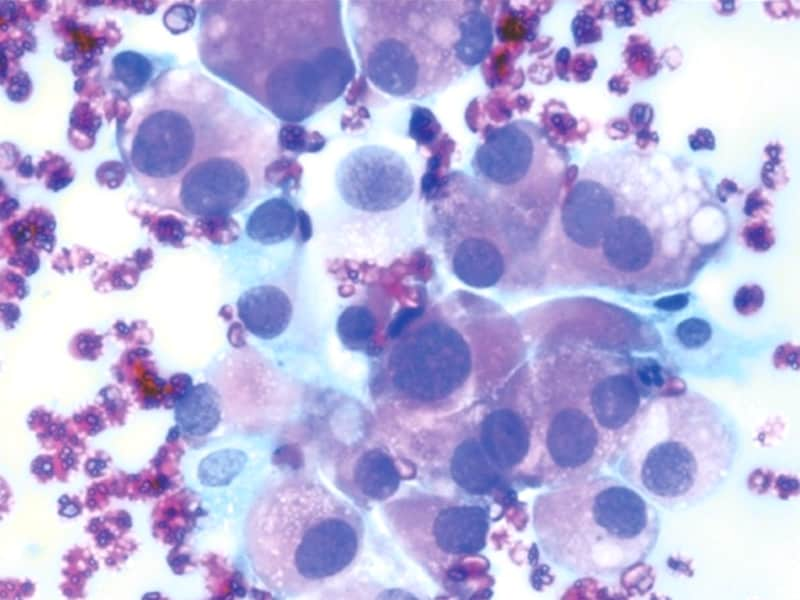

Фотографии опухоли медуллярной аденокарциномы

Раздел: Снимки-откровения